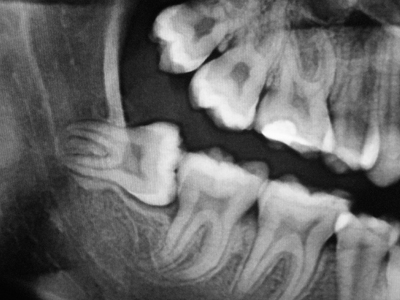

Alcuni esempi di patologie orali